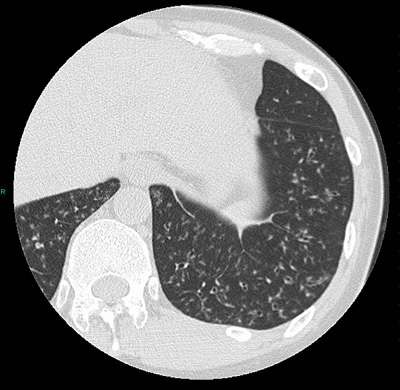

この病気の診断には、肺のCT検査が非常に重要であり、細い気管支に炎症がひろがるため肺に小さい粒のような影がみられます。たんの検査からインフルエンザ菌、肺炎球菌が検出され、進行例では緑膿菌が検出されます。呼吸機能検査では閉塞性障害がみられます。

胸部CT所見:両方の肺に小さい粒のような陰影がみられます。